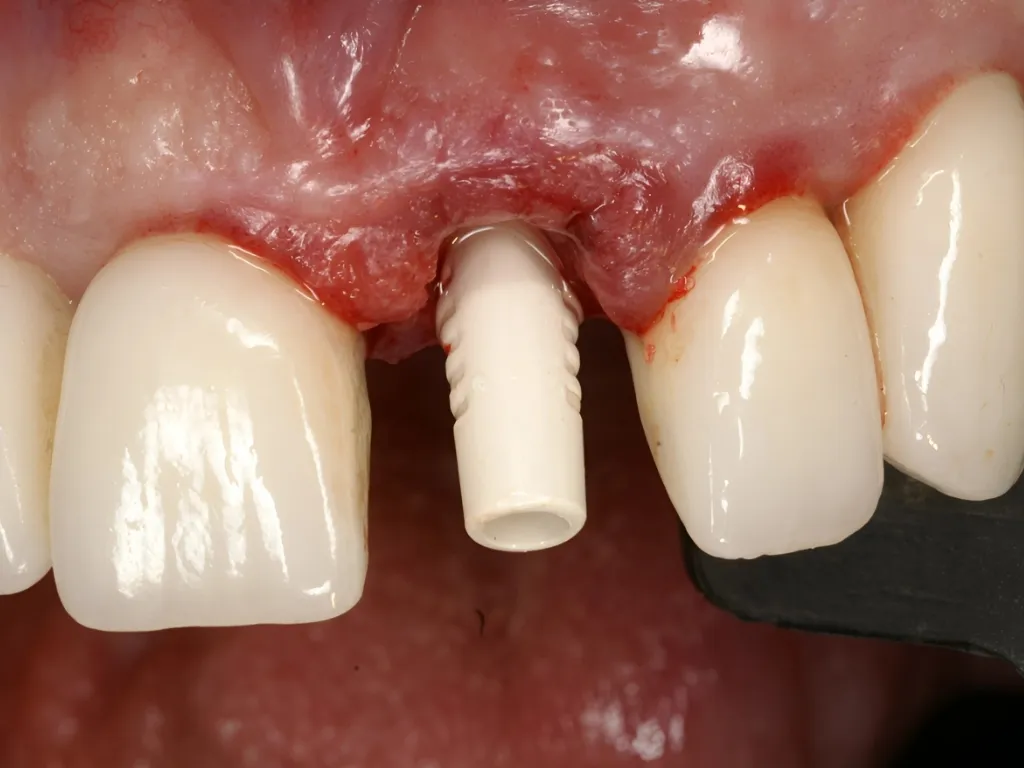

vaka_img

Otojen Kemik Grefti ile Çekim Sonrası İmplant

Dr. Manuel de la Rosa